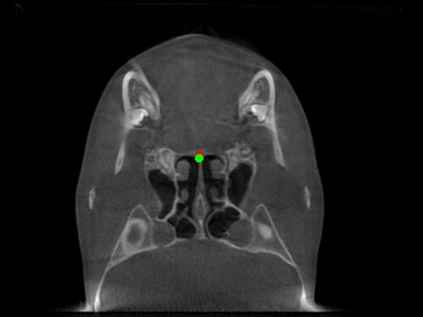

Detecting 3D landmarks on cone-beam computed tomography (CBCT) is crucial to assessing and quantifying the anatomical abnormalities in 3D cephalometric analysis. However, the current methods are time-consuming and suffer from large biases in landmark localization, leading to unreliable diagnosis results. In this work, we propose a novel Structure-Aware Long Short-Term Memory framework (SA-LSTM) for efficient and accurate 3D landmark detection. To reduce the computational burden, SA-LSTM is designed in two stages. It first locates the coarse landmarks via heatmap regression on a down-sampled CBCT volume and then progressively refines landmarks by attentive offset regression using multi-resolution cropped patches. To boost accuracy, SA-LSTM captures global-local dependence among the cropping patches via self-attention. Specifically, a novel graph attention module implicitly encodes the landmark's global structure to rationalize the predicted position. Moreover, a novel attention-gated module recursively filters irrelevant local features and maintains high-confident local predictions for aggregating the final result. Experiments conducted on an in-house dataset and a public dataset show that our method outperforms state-of-the-art methods, achieving 1.64 mm and 2.37 mm average errors, respectively. Furthermore, our method is very efficient, taking only 0.5 seconds for inferring the whole CBCT volume of resolution 768$\times$768$\times$576.